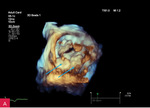

Rycina 4A, B. Badanie echokardiograficzne przezklatkowe trójwymiarowe (3D TTE) – widok od strony lewej komory zastawki mitralnej i guzowatej zmiany o nierównej powierzchni (A) wraz z prezentacją zmiany w przekrojach wykonanych na podstawie 3D TTE (B)